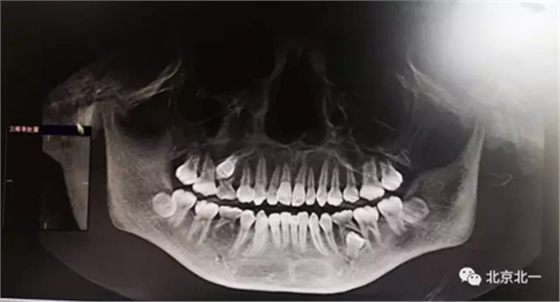

圖一:拔牙前影像片(CBCT)